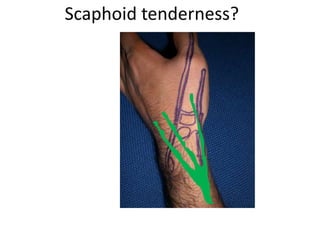

- Naming the bones, joints, tendons, nerves and skin landmarks of the hand and wrist.